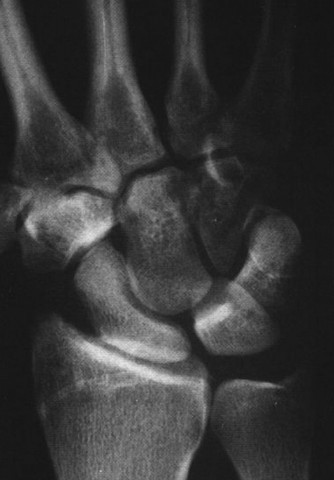

CASE 11 A patient presents to your clinic with ulnar-sided wrist pain. X-ray is…

CASE 27 Several years after sustaining an injury to his wrist, a firefighter pr…